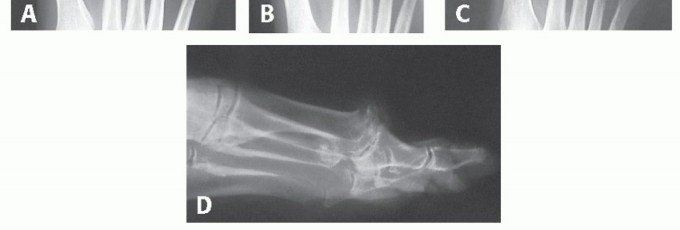

Guide Pin Placement for HemiCAP DF

Place the centering spherical guide for the 15-mm HemiCAP on the metatarsal head with the feet of the guide in a superoinferior position. A 15-mm guide is used typically; only on rare occasions is a 12-mm guide used as an alternative with an anatomically small head. Alternatively, the guide pin can be placed freehand on surgeon preference.

During this step, particular importance should be paid to (1) location of the starting point and (2) pin trajectory on the AP and lateral views for ultimate alignment of the implant is based off of this first step. The importance of this step cannot be understated. We suggest entering the head only slightly and then checking AP and lateral fluoroscopic images, thereby making adjustments prior to committing. Note: Starting point is more plantar than what appears to be the center of the metatarsal head; also, the inclination angle of the metatarsal is greater than one would think so must drop hand while drilling.

- TECH FIG 1 • Guide pin placement. A. Intraoperative picture of spherical guide placement just above the crista of the first metatarsal. B. AP view of pin placed in line with the long axis of the first MTP shaft. C. Lateral image of pin placed parallel to the long axis of the MTP shaft. The surgeon can drop his or her hand as necessary to match the inclination of metatarsal and midline within the shaft. (continued)

The perimeter of the guide should not violate the metatarsosesamoid complex and its inferior border is

generally seated just above the crista. Avoid malplacement of the guide pin by plantarflexing the guide as necessary to adjust for normal inclination of the metatarsal shaft. It is critical that this be in line with the long axis of the metatarsal shaft on the lateral fluoroscopic view.

Place the centering guide pin on the metatarsal head in line with the long axis of the metatarsal shaft and verify its position on AP and lateral fluoroscopic views. Adjust the guide pin as necessary to obtain correct placement (TECH FIG 1A-E). Pay particular attention to the guide pin lateral view, for there is a tendency to underestimate the degree of inclination of the metatarsal shaft; parallel to the long axis of the shaft is the desired position. Adjust the pin before proceeding.